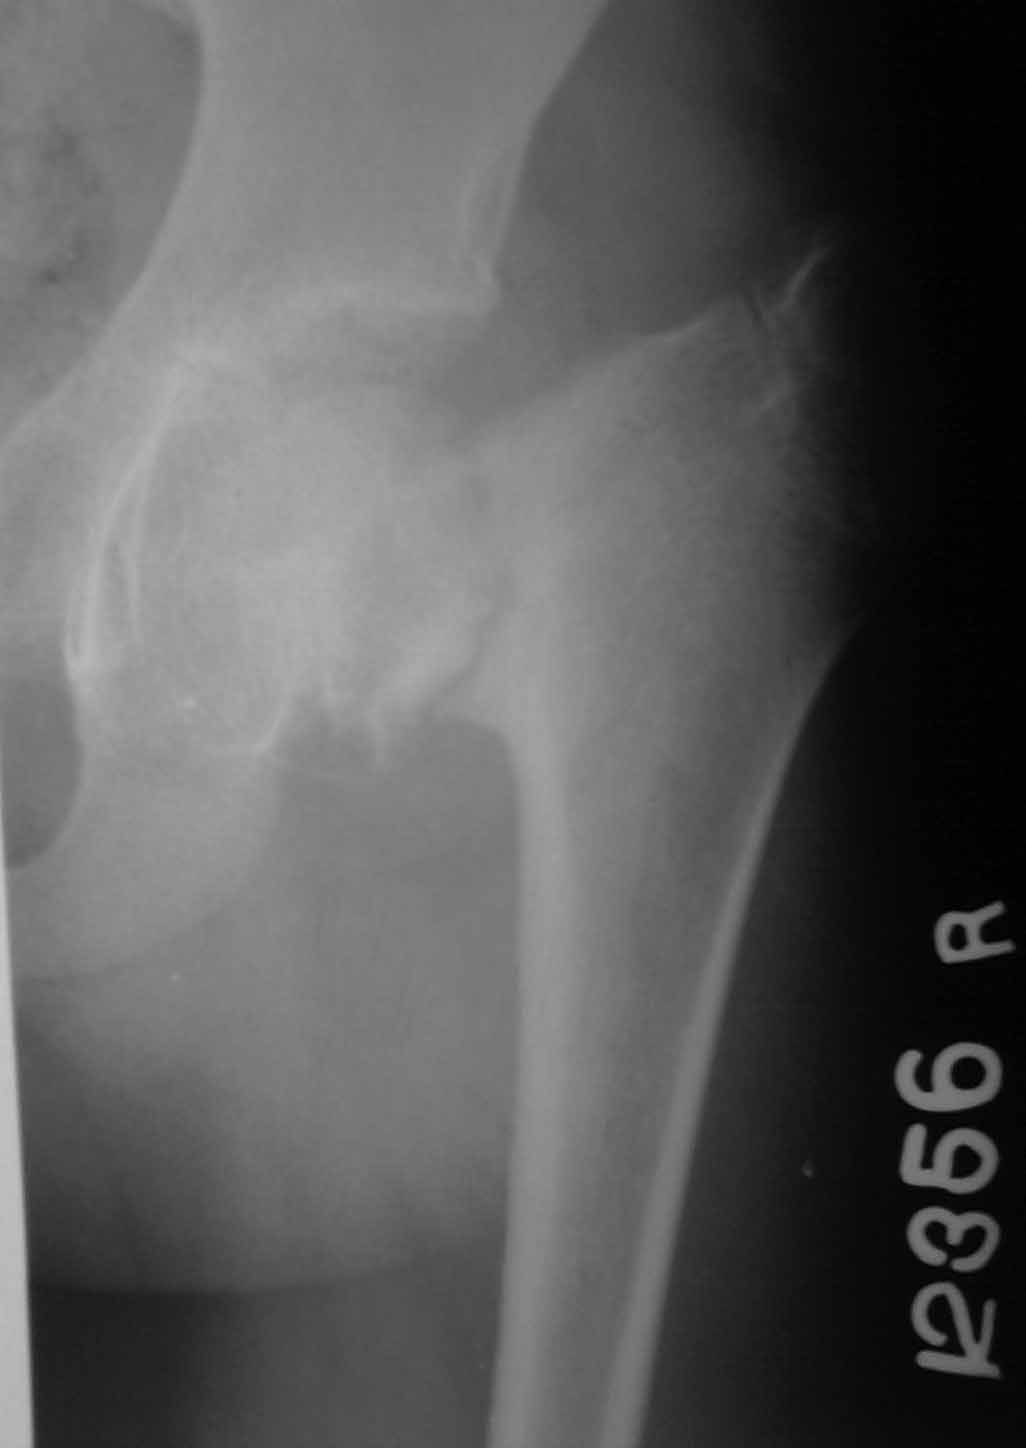

Paediatric old neglected # NOF

K mne prishla devochka 11 let.

Jalabi; na bol v oblasti pravogo HIP joint.

Uctoriya bolezni; trauma god nazad, ni obrashalas k vrachu... Prinimala paracetamol dlya boli.

Osmotr: ukorocheniye hijnoi konechnosti na 2.5 cm. Local tenderness in the region of rt greater trochanter. Range of motion; almost full but painful.

Xray; fracture neck of femur.

For my opinion this is an old process, more than one year. It very similar to Congenital Coxa Vara.

Treatment - valgus osteotomy. Very important to achieve correct orientation of the growth plate (compare with opposite hip)

I agree with previous doc. It is not fracture, but so-called coxa vara coli lysis - zone of bone tissue reconstruction.